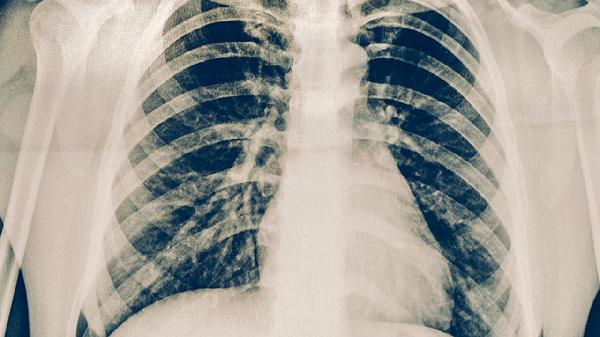

肺结核患者需遵医嘱使用异烟肼片、利福平胶囊、吡嗪酰胺片、乙胺丁醇片、链霉素注射液等抗结核药物联合治疗。肺结核是由结核分枝杆菌感染引起的慢性传染病,需规范用药6-9个月,药物组合需根据耐药性检测结果调整。

肺结核患者应严格遵循早期、联合、适量、规律、全程的用药原则,完成规定疗程避免复发。治疗期间保持高蛋白高维生素饮食,适当补充牛奶鸡蛋瘦肉等优质蛋白。注意隔离防护避免传染他人,定期复查胸部影像学和痰菌检查。出现药物不良反应需及时就医调整方案,切忌自行停药或更改剂量。保持居室通风良好,保证充足睡眠有助于康复。